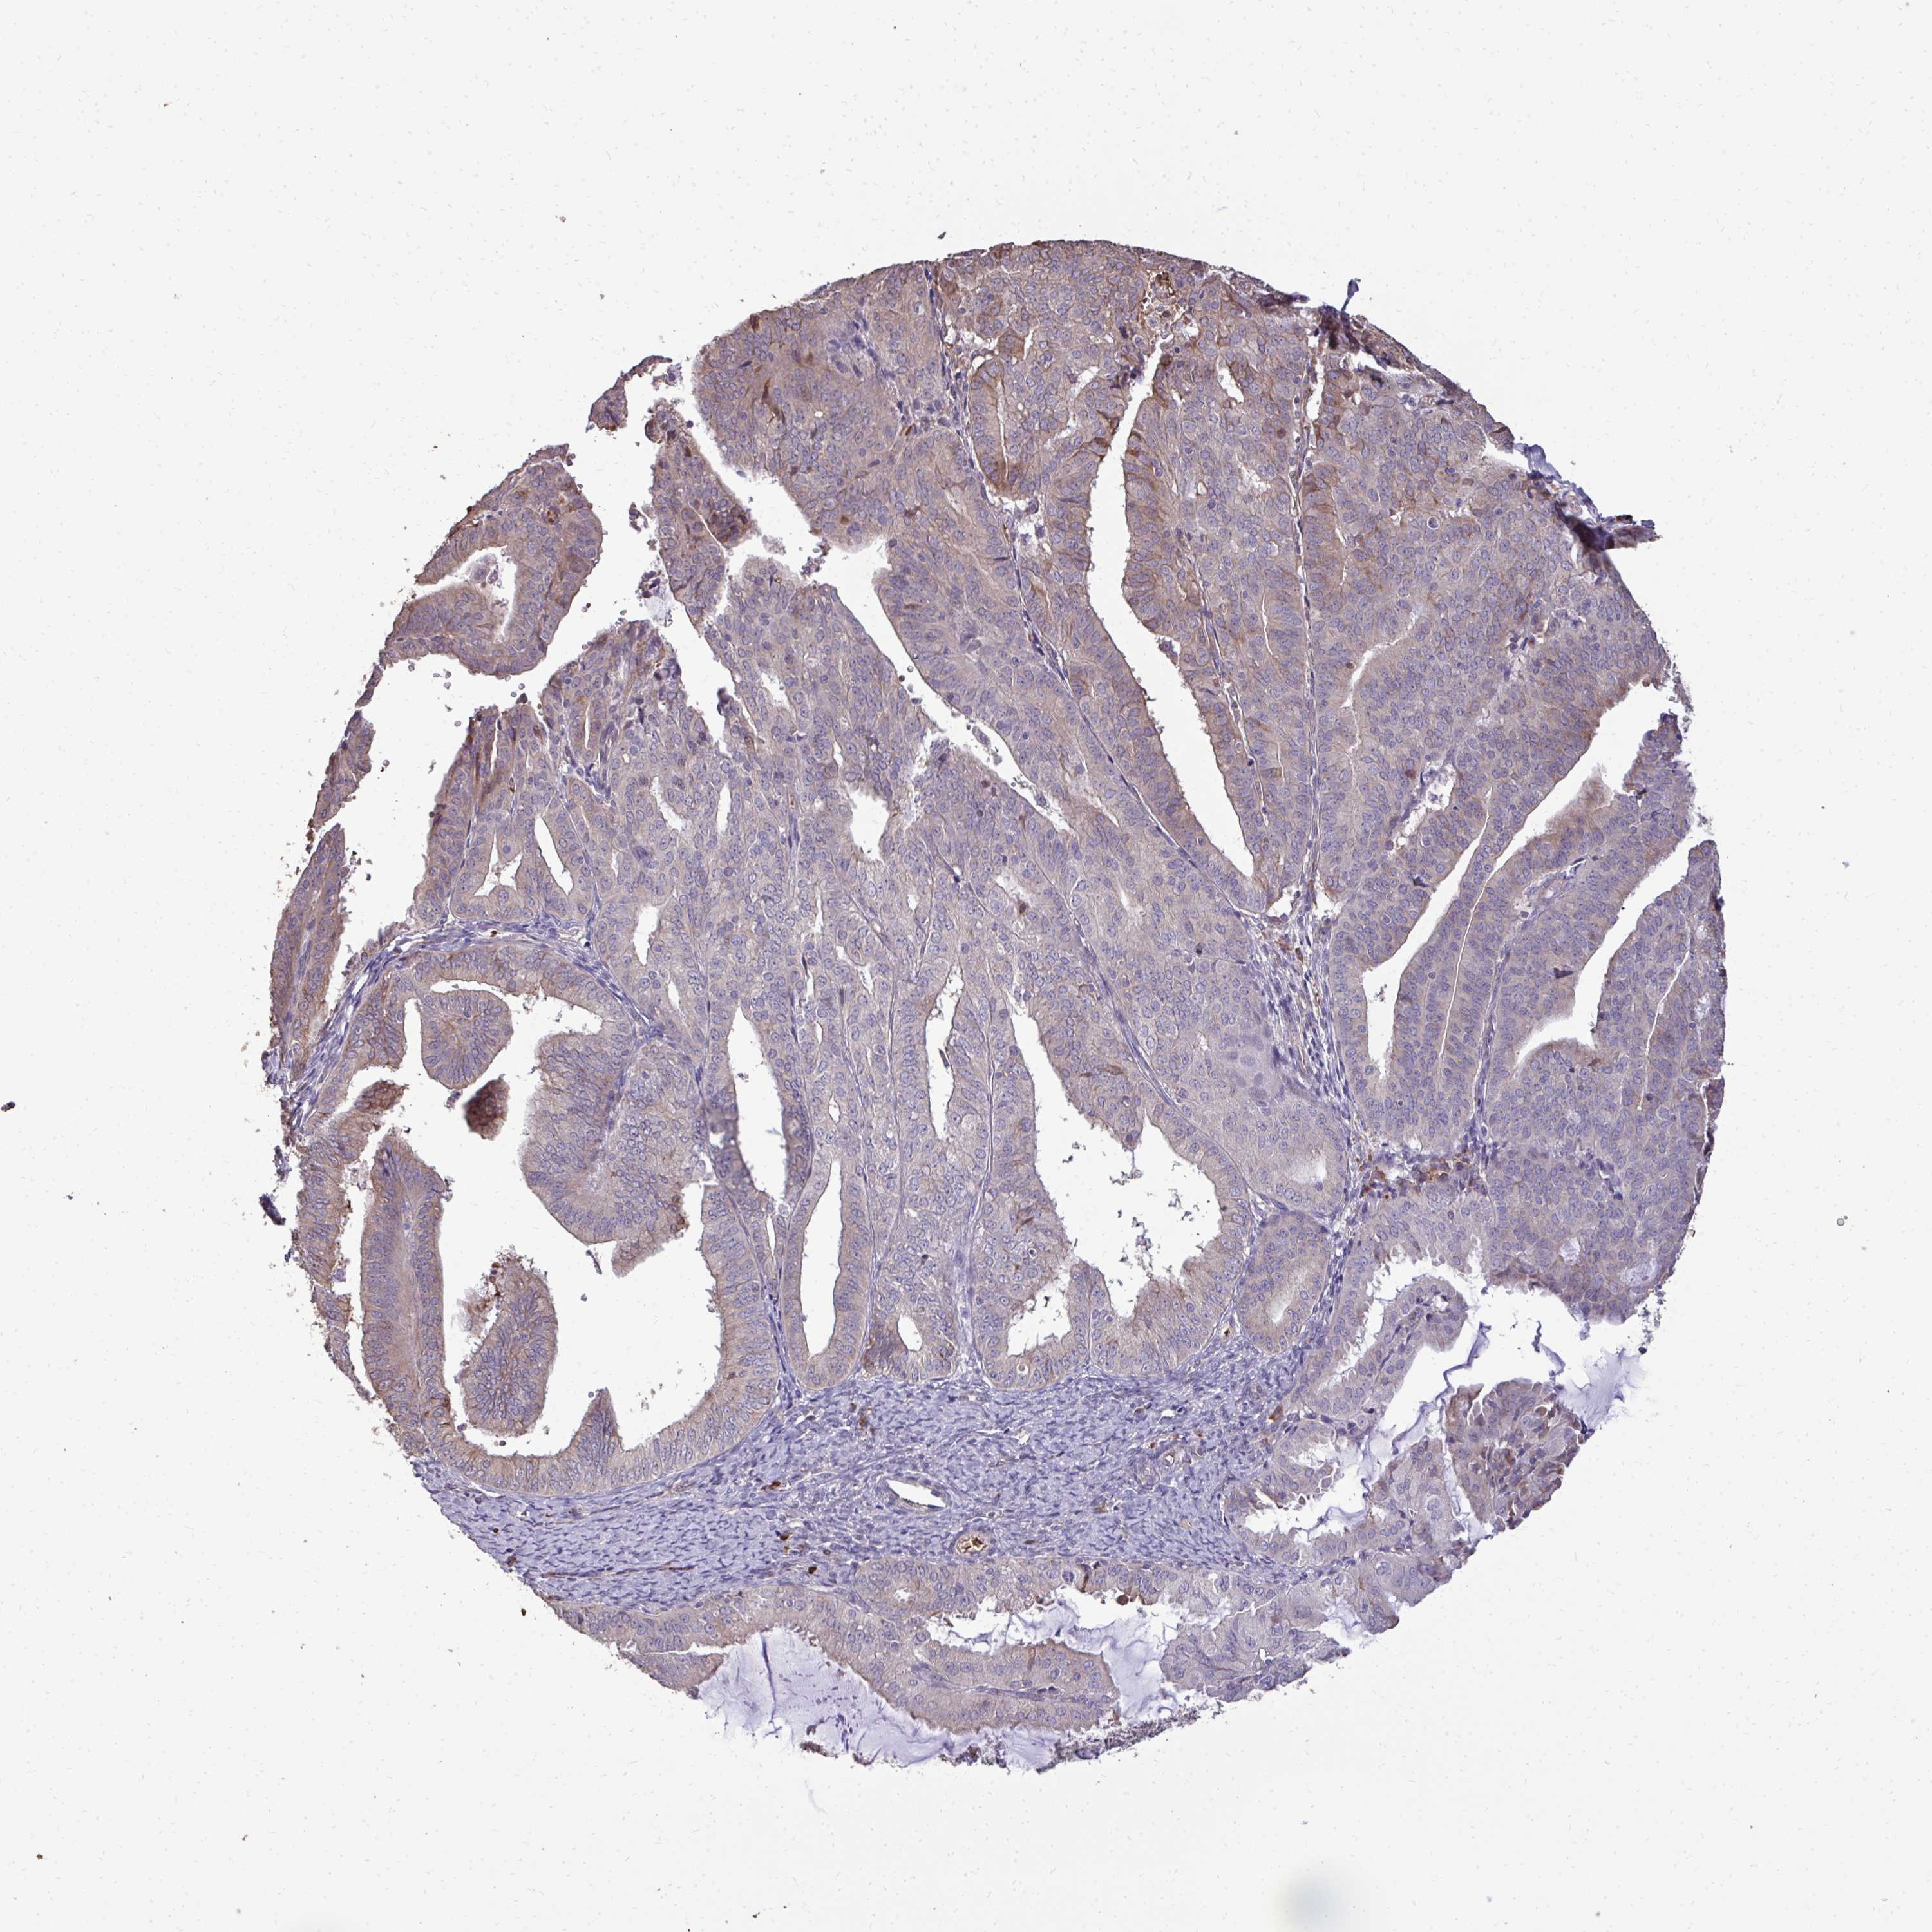

ENDOMETRIAL CANCER - Protein expressioni

A mouse-over function shows sample information and annotation data. Click on an image to view it in a full screen mode. Samples can be filtered based on level of antibody staining by selecting one or several of the following categories: high, medium, low and not detected. The assay and annotation is described here.

Note that samples used for immunohistochemistry by the Human Protein Atlas do not correspond to samples in the TCGA dataset.

Antibody stainingi

Antibody staining in the annotated cell types in the current human tissue is reported as not detected, low, medium, or high, based on conventional immunohistochemistry profiling in selected tissues. This score is based on the combination of the staining intensity and fraction of stained cells.

Each image is clickable and will lead to virtual microscopy that enables deeper exploration of all samples and also displays staining intensity scores, fraction scores and subcellular localization as well as patient and tissue information for each sample.

Antibody HPA055353

Staining

High

Medium

Low

Not detected

Intensity

Strong

Moderate

Weak

Negative

Quantity

>75%

75%-25%

<25%

None

Location

Nuclear

Cytoplasmic/membranous

Cytoplasmic/membranous,nuclear

Adenocarcinoma, NOS